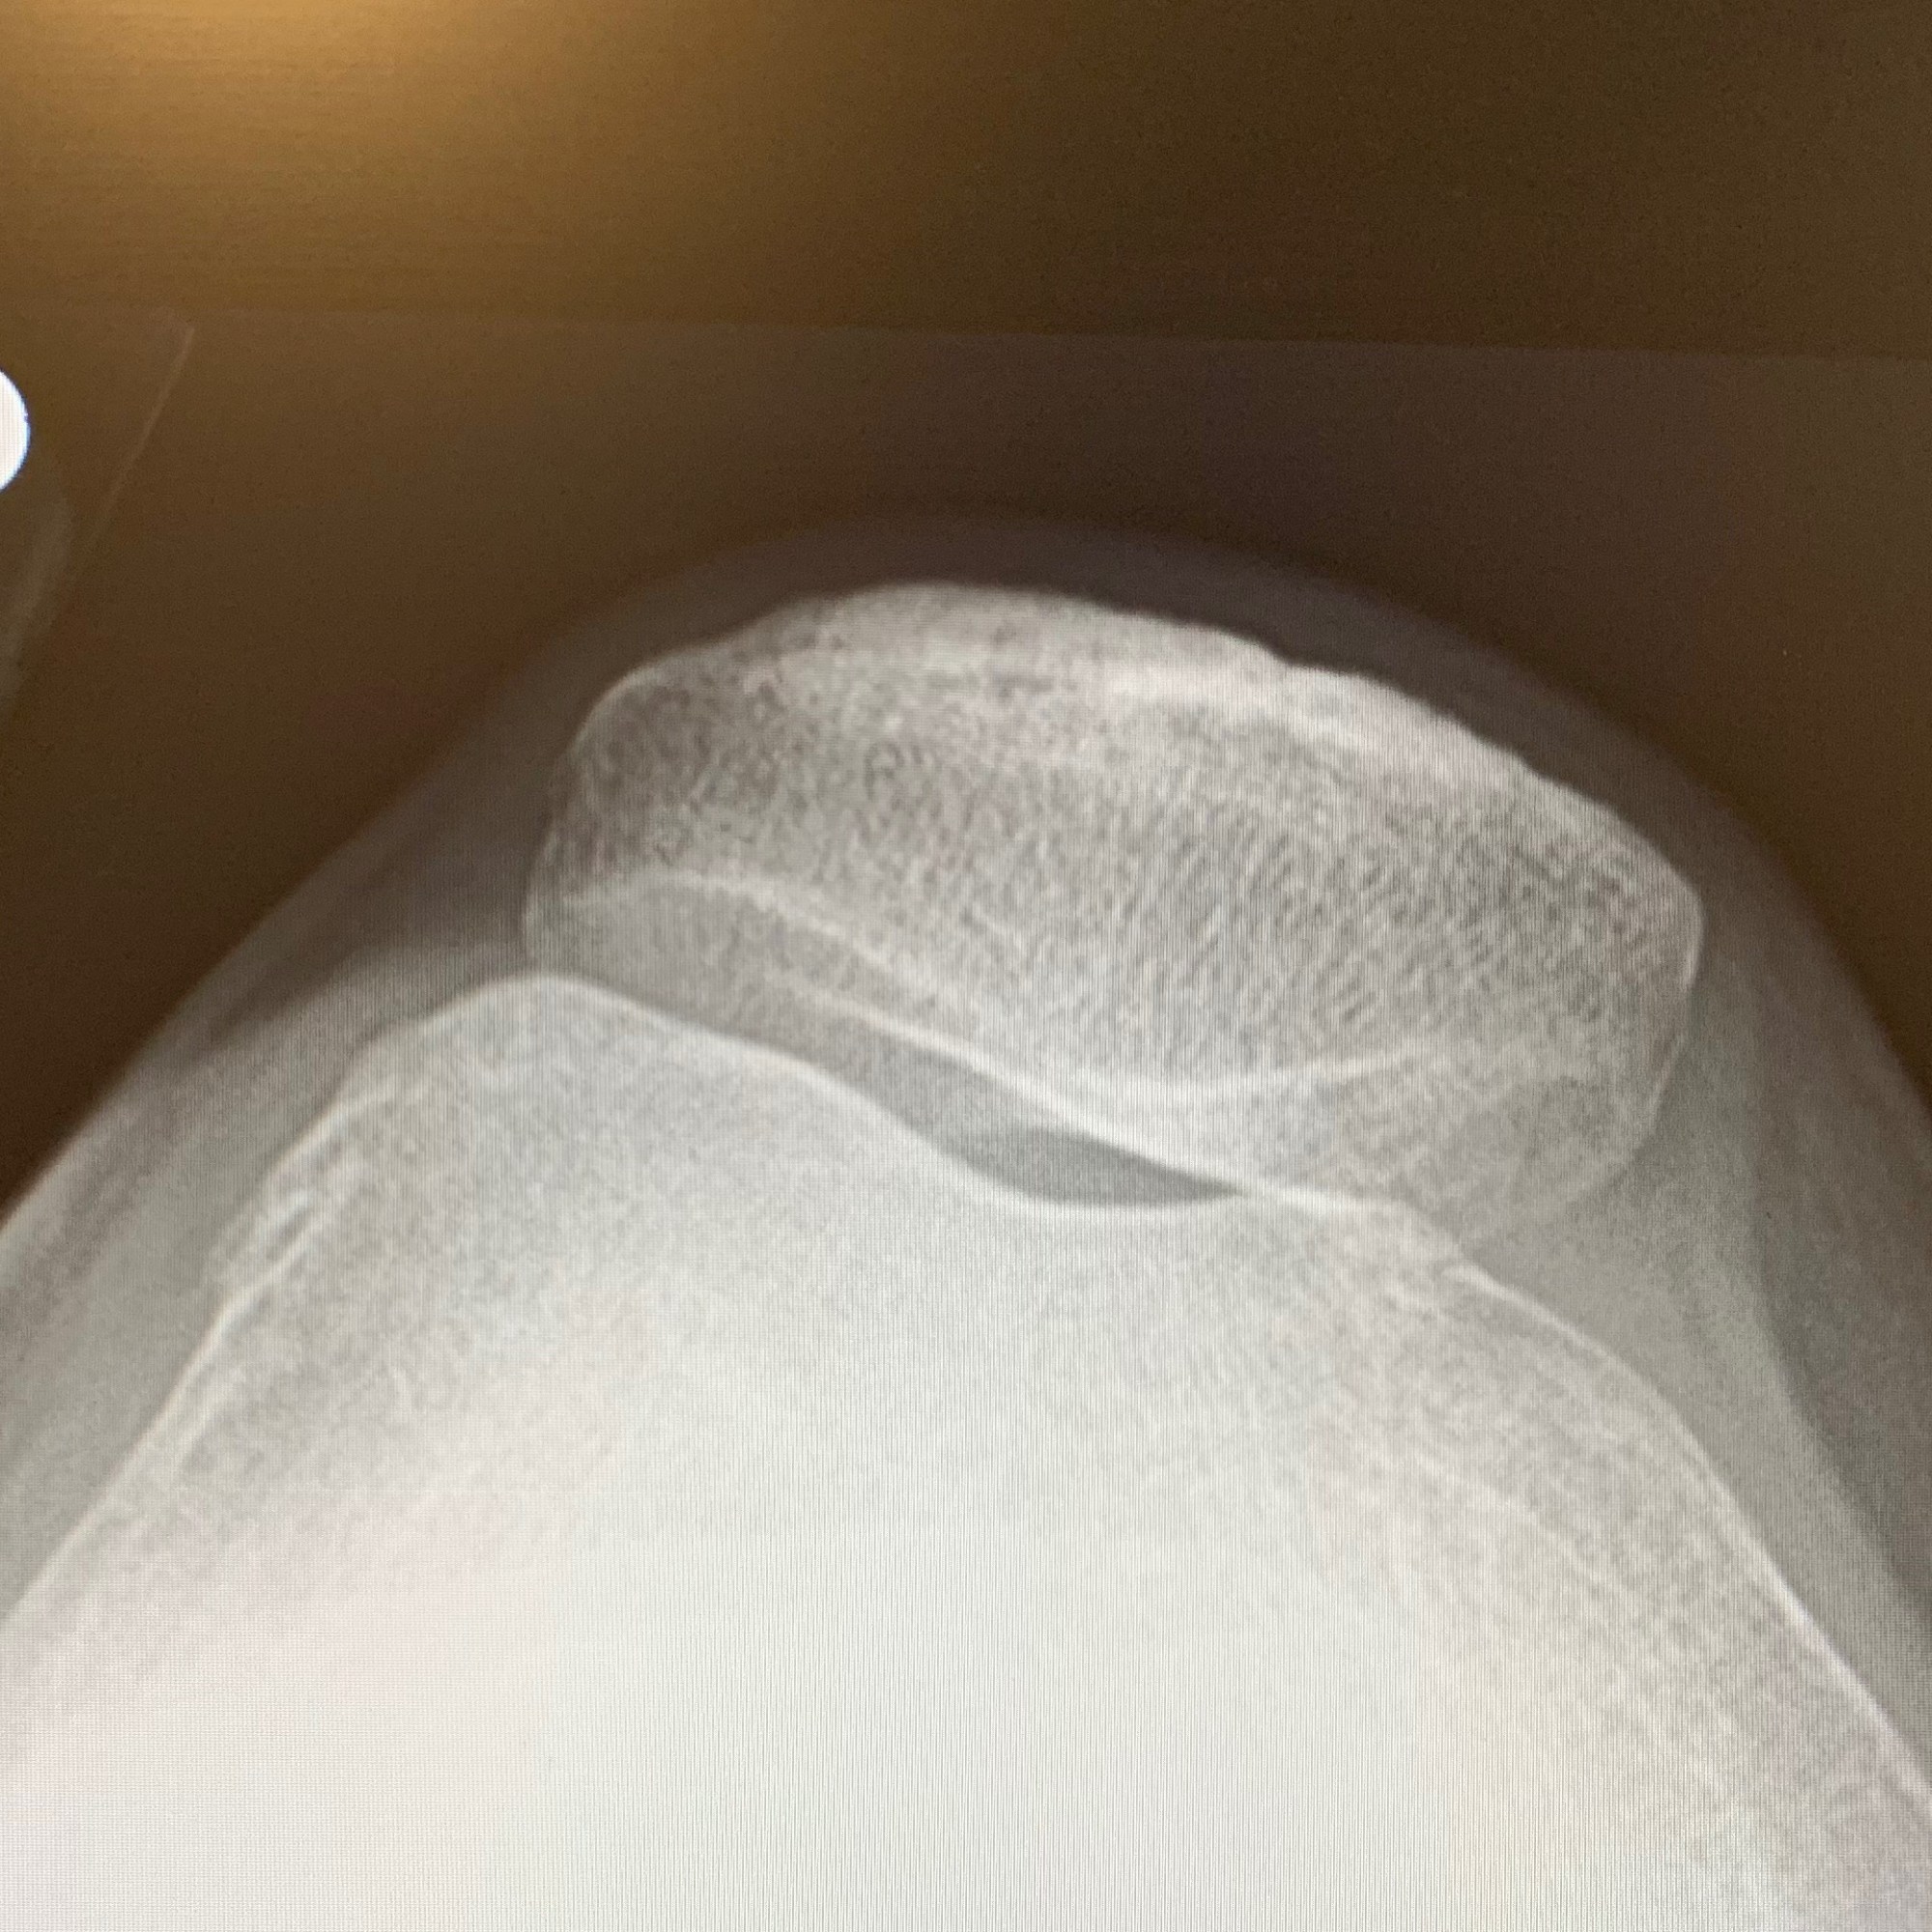

In May (just as Diane Hiller, medical intuitive had predicted) I had my 6th joint replacement/12th surgery (not including two c-sections); for the injured knee that had been “loose” since I was a kid. It had finally begun to really hurt and made stairs or any amount of standing/walking vey painful. When it came time to have it done, I went to one of the best orthopedic surgeons — Dr. Perry Green. I had met Dr. Green 22 years ago when he performed my very first joint replacement in 1999 — my left hip shown here, which is still going strong to this day! You can also see my Lower Lumber Fusion – 2010 also going strong!